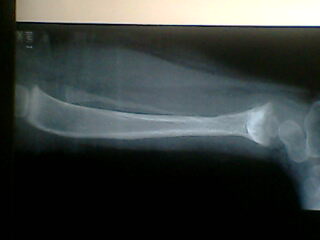

标题: PED0257:小腿

小孩腿痛波形

腓骨骨质溶解,大块骨质溶解症可能性大,建议进一步询问病史,进一步检查。有既往片价值更高。

左腓骨呈容骨性破坏。骨皮质及骨髓腔均破坏,下段骨不连续,周围软组织肿胀。考虑骨尤文氏肉瘤可能性大。

尤文肉瘤的明显软组织肿块与较小骨质破坏不成比例,本例似乎不符合。应考虑腓骨骨质溶解,建议询问家族史。